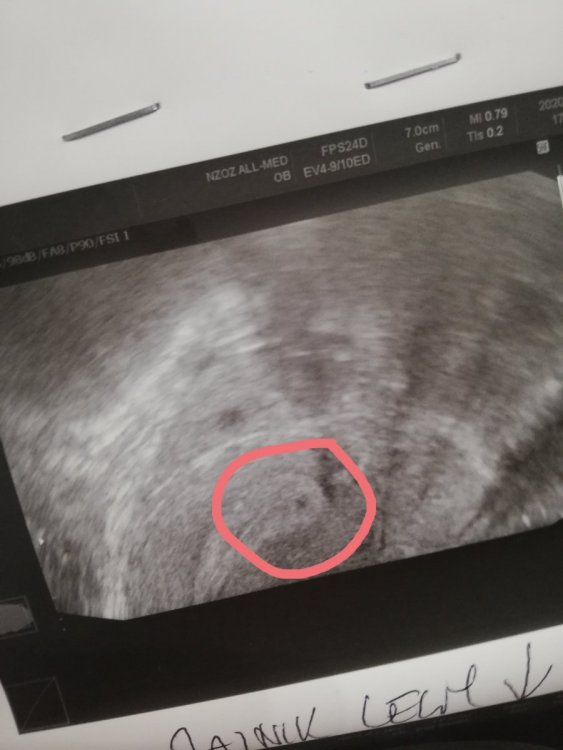

i za dwa dni serduszko na usg :-)